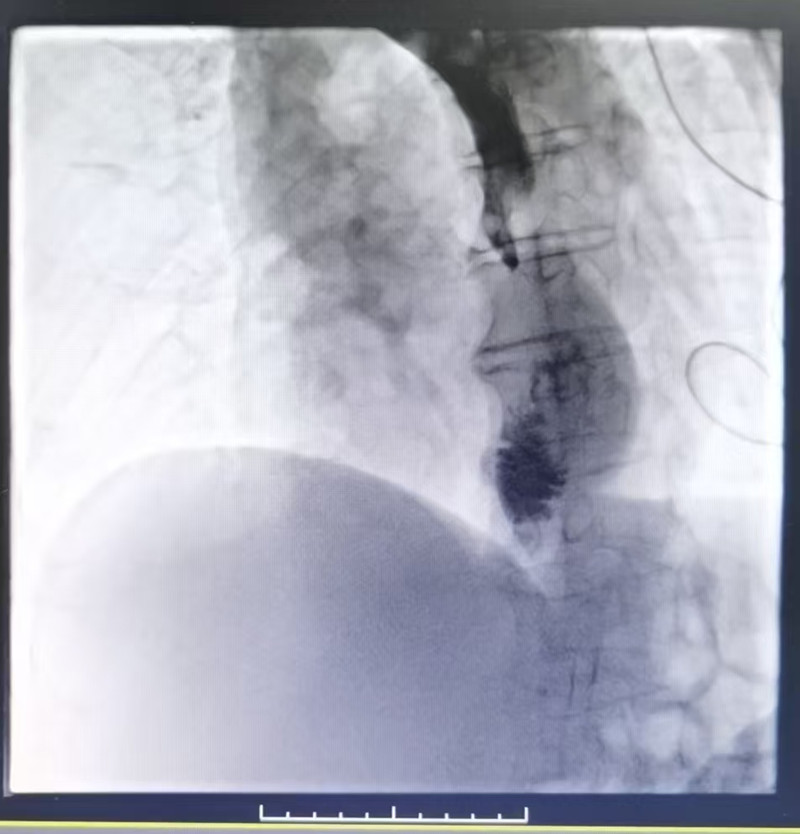

术前造影剂通过迟缓

据了解,该患者贲门癌术后4年余,肺转移8月余,进食梗阻1月余。近20天患者出现声音嘶哑,进行性加重,自诉伴进食哽噎感,今患者为求进一步抗肿瘤治疗入住我院区。食管口服造影剂示胃上提至胸腔,吻合口处约5cm管壁僵硬,管腔狭窄,造影剂通过明显受阻,黏膜纹破坏中断,同时胃镜检查不能通过。家人考虑到手术风险及患者心理承受能力等情况,希望用创伤最小的治疗缓解患者症状。肿瘤内科负责人、副主任医师陶黎明带领科室团队反复询问病史及评估患者情况,和患者家人商定,行食管支架植入术,完美演绎了从食管梗阻至顺利通畅的全过程。